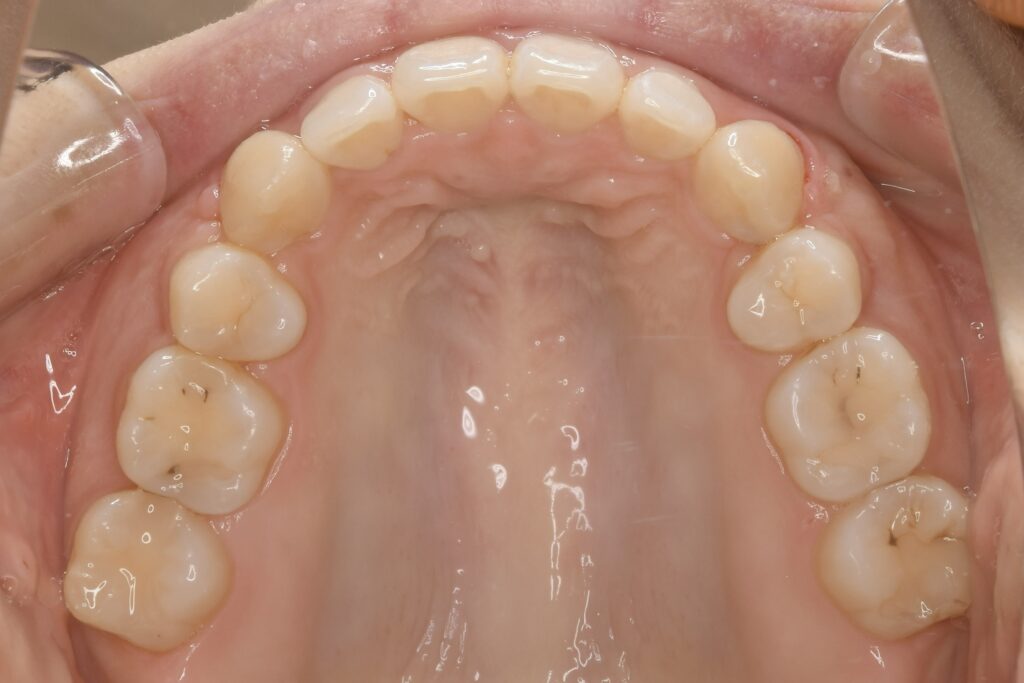

32歳 女性 治療期間:1年7ヶ月

AFTER

治療内容 上下とも歯を2本抜いて、上の前歯を後方に引きながら、でこぼこを治しました。

抜歯部位 上 両側4番目

下 右側4番目、左側5番目